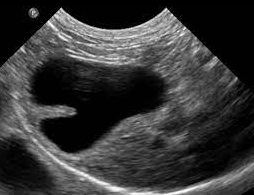

고양이 2중 담낭에 대한 분류

보통 고양이 복부 초음파를 볼때 담낭이 2개인 친구들이 종종 관찰된다.

분류를 하다보면 나중에 뭔가 새로운 사실이 발견되기도 하기에 연구자들은 항상 분류를 하려고 노력한다.